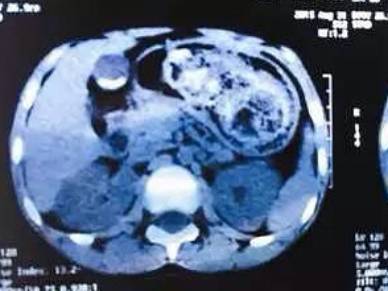

CT片显示,右上为患儿的胃,几乎被结石占满,黑色部分为所剩空间。

“头发在胃里很难消化,而且会和其他食物缠绕,时间一长,缠绕的越来越厉害,逐渐形成了巨大的胃石,最终堵塞胃肠道。”肖东表示,通过ct检查发现,石头已经占据了胃里90%的空间,无法通过胃镜取出来,只能通过手术取出胃石。